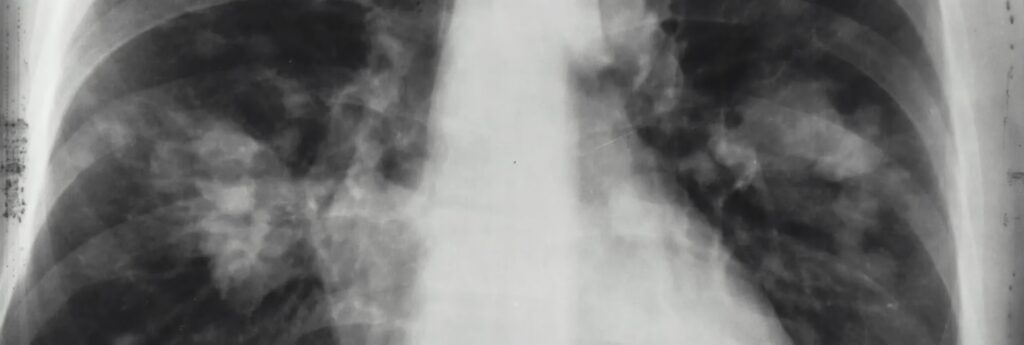

Når det kommer til CAP, er billeddiagnostik afgørende. Et røntgenbillede af thorax er normalt det første skridt: det er hurtigt, tilgængeligt og nyttigt til at opdage infiltrater, konsolideringer eller pleurale effusioner. Men det har sine begrænsninger – især i de tidlige stadier af sygdommen eller hos patienter med f.eks. KOL, hvor lungebilledet i forvejen kan være forandret.

Når det kliniske billede er uklart eller mere komplekst, bliver en CT-scanning et værdifuldt værktøj. Med større nøjagtighed hjælper den med at differentiere lungebetændelse fra andre lungesygdomme, såsom lungeemboli eller atelektase. Ulempen? Radiologiske rapporter kommer ikke altid hurtigt tilbage, hvilket kan forsinke opstarten af behandlingen.

AI-drevne værktøjer kan nu fortolke billeddiagnostiske undersøgelser i realtid og med høj nøjagtighed detektere mønstre, der er forenelige med lungebetændelse. Moderne teknologier kan analysere røntgen- og CT-billeder og levere komplette rapporter på så lidt som 60 sekunder – uden at kræve menneskelig indgriben i første omgang. Denne tidsbesparelse har en direkte indvirkning på både kliniske beslutninger og administrative processer. Når rapporter leveres rettidigt, kan hospitaler registrere procedurer korrekt og sikre refusion fra forsikringsselskaber og offentlige programmer.